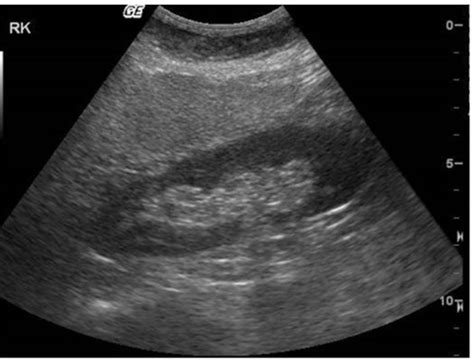

Alright, let’s get down to the nitty-gritty of what fatty liver infiltration actually means, especially when it’s described as mild . Imagine your liver, that incredible organ working tirelessly behind the scenes, processing everything you eat and drink. One of its many jobs is to handle fats (lipids). It takes fats from your diet, makes them, and helps transport them out to where your body needs them. Now, fatty liver, or more technically, hepatic steatosis, happens when there’s an excessive accumulation of fat within the liver cells. When we say ‘mild fatty infiltration,’ it means this fat buildup is present but hasn’t reached a level that causes significant damage or inflammation to the liver. Think of it as a slight overflow in the fat storage department of your liver factory. It’s not a full-blown crisis, but more like a gentle nudge that says, ‘Hey, maybe we should pay a little more attention to how we’re handling fats.’ This mild accumulation usually doesn’t cause any noticeable symptoms, which is why it’s often discovered by chance during an ultrasound or CT scan ordered for something else. The liver appears brighter or ‘hyperechoic’ on an ultrasound because fat reflects sound waves differently than normal liver tissue. This appearance is the hallmark of fatty infiltration. It’s crucial to understand that the liver is remarkably resilient. In its mild form, fatty infiltration typically doesn’t impair the liver’s function. The liver cells are still doing their jobs, processing nutrients, detoxifying your blood, and producing bile. However, it’s a warning sign . It signals that the balance of fat metabolism in your body is off. This imbalance could be due to a number of factors, ranging from diet and weight to underlying health conditions. The liver’s ability to store fat is significant, but when fat intake or production consistently outpaces the liver’s capacity to process and export it, steatosis occurs. This is particularly common in conditions like obesity and type 2 diabetes, where insulin resistance plays a major role. Insulin resistance can promote fat storage in the liver and inhibit the release of fat from the liver. So, while ‘mild’ sounds reassuring, it’s your body’s way of giving you a heads-up. It’s an opportunity to make changes before the condition potentially progresses to more serious forms like steatohepatitis (fatty liver with inflammation), fibrosis (scarring), or even cirrhosis (severe scarring). So, in simple terms, mild fatty infiltration is a sign of excess fat in the liver cells, usually without immediate harm but indicating an underlying metabolic imbalance that needs attention.

Okay, so you’ve heard the term mild fatty infiltration of the liver , and now you’re wondering, ‘How do doctors even figure this out?’ The diagnostic process usually starts with your doctor considering your medical history and risk factors . They’ll ask about your diet, exercise habits, weight changes, family history of liver disease, alcohol consumption, and any medications you’re taking. They’ll also be on the lookout for signs of conditions strongly associated with fatty liver, like obesity, diabetes, metabolic syndrome, high cholesterol, and high triglycerides. Based on this information, they might order some tests. The gold standard for diagnosing the presence and severity of fat in the liver is usually through imaging studies . The most common and often the first line of investigation is an abdominal ultrasound . This non-invasive test uses sound waves to create images of your organs. In fatty liver, the liver tissue appears brighter (hyperechoic) on the ultrasound compared to the surrounding tissues, like the spleen or the right kidney. The radiologist can also often grade the severity of the fatty infiltration as mild, moderate, or severe based on how much the liver tissue appears brighter. Another imaging option is a CT scan or MRI (Magnetic Resonance Imaging). These can also detect fat in the liver and provide more detailed images, sometimes differentiating between simple fatty liver and more complex conditions. MRIs, in particular, can offer more precise measurements of fat content. Now, what about blood tests ? While blood tests can’t directly diagnose fatty liver, they are crucial for assessing overall liver health and ruling out other causes of liver problems. Your doctor will likely order a liver function panel , which includes tests like ALT (alanine aminotransferase), AST (aspartate aminotransferase), ALP (alkaline phosphatase), and bilirubin. In mild fatty liver, these enzymes might be normal or only slightly elevated. Significantly high levels often suggest inflammation or damage, pointing towards non-alcoholic steatohepatitis (NASH) or other liver diseases. Other blood tests might check for viral hepatitis (like Hepatitis B or C), autoimmune markers, and iron levels to exclude other potential causes of liver disease. Sometimes, especially if there’s a concern about scarring (fibrosis) or inflammation, a doctor might consider a transient elastography (like FibroScan), which is a non-invasive ultrasound-based test to measure liver stiffness. In cases where the diagnosis is uncertain or there’s suspicion of significant inflammation or fibrosis, a liver biopsy might be recommended. This is the most definitive way to diagnose and stage liver disease, but it’s an invasive procedure, so it’s usually reserved for more complex situations. For most cases of mild fatty infiltration, imaging like an ultrasound is sufficient for diagnosis, often coupled with blood tests to check for associated metabolic issues.